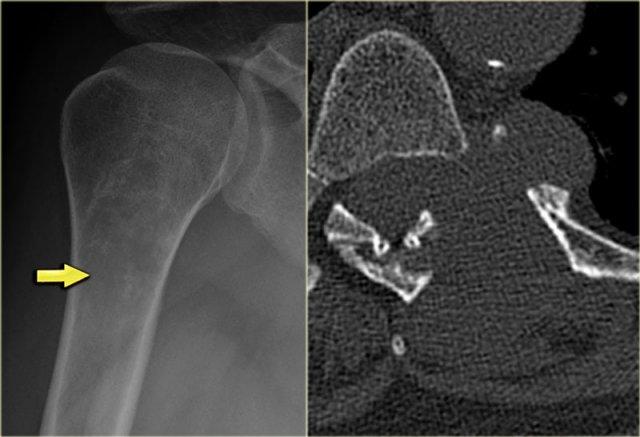

Bên trái là tổn thương hỗn hợp tiêu xương và xơ cứng ở đầu trên xương cánh tay với phá hủy vỏ xương không đều.

Có phản ứng màng xương xâm lấn và khối phần mềm.